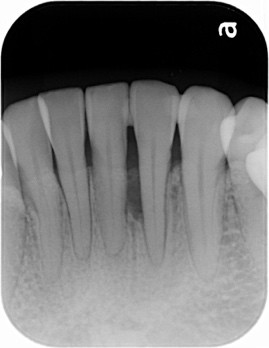

Before

治療方法:患部の清掃・再生のお薬(エムドゲイン)・自家骨の移植により骨の再生を促します。

治療結果:歯茎からの出血や膿が止まり、さらに骨の再生が確認できた。